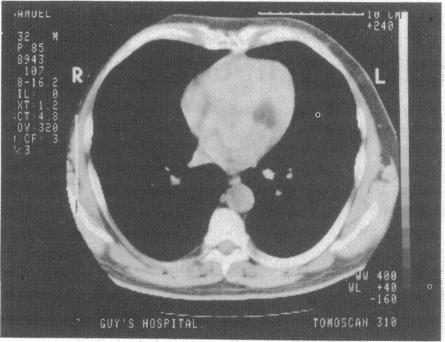

A 54 year old man presented with presyncopal symptoms. Echocardiography and subsequently computed tomography showed a mass in the posterior mitral annulus causing incompetence of the valve. At operation a lipoma was found which could not be resected. Mitral incompetence was the result of chordal rupture where the lipoma had engulfed the papillary muscle. The valve was replaced and the patient made an uneventful recovery. This case report shows a potential danger of an otherwise benign lesion.

一名54岁男性出现晕厥前症状。超声心动图检查以及随后的计算机断层扫描显示二尖瓣后瓣环处有一肿块,导致瓣膜关闭不全。手术中发现是一个无法切除的脂肪瘤。二尖瓣关闭不全是由于脂肪瘤包绕乳头肌导致腱索断裂所致。患者接受了瓣膜置换手术,术后恢复顺利。本病例报告显示了一种原本良性的病变可能存在的危险。